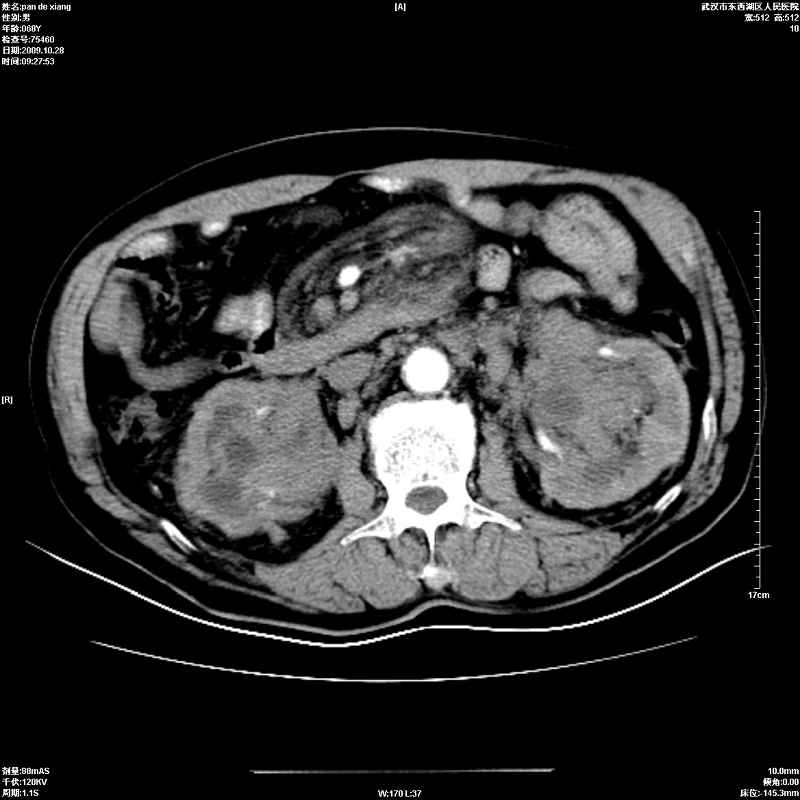

以下是引用杀毒软件在2009-10-28 20:41:00的发言:[br]结合临床考虑---白血病双肾改变或淋巴瘤。

以下是引用zxl51642在2009-10-29 9:59:00的发言:[br]结合临床“单克隆免疫球蛋白血症”,考虑双肾为继发损害并肾功能不全(尿中大量igg及少量iga、igm等大分子免疫球蛋白滤出所致继发损害),椎前软组织肿块为髓外造血。与浆细胞瘤有区别,平扫时有战友说的很清楚。